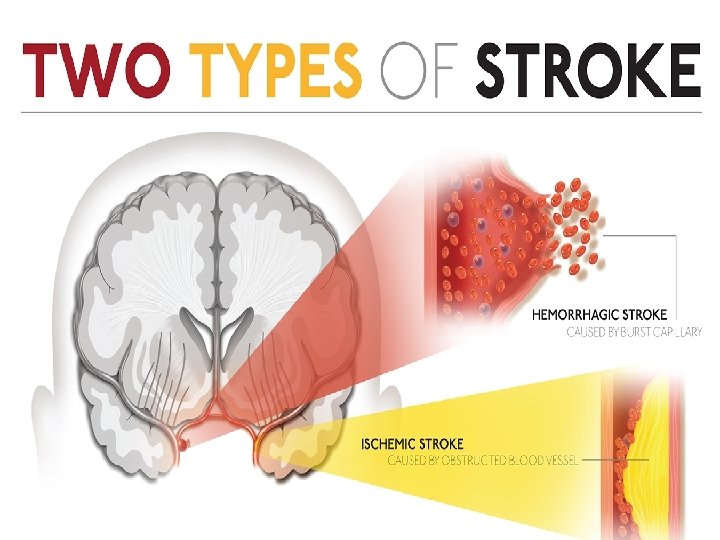

Stroke Ischaemic stroke/infarction (80%) Ø Thrombotic Ø Cardio-embolic Ø Large artery stenosis Ø Small vessel disease Ø Hypoperfusion Haemorrhagic stroke (17%) Ø Intracerebral hemorrhage (12%) Ø Subarachnoid hemorrhage (5%) Other (3%), e. g. arterial dissection, venous sinus thrombosis, vasculitis